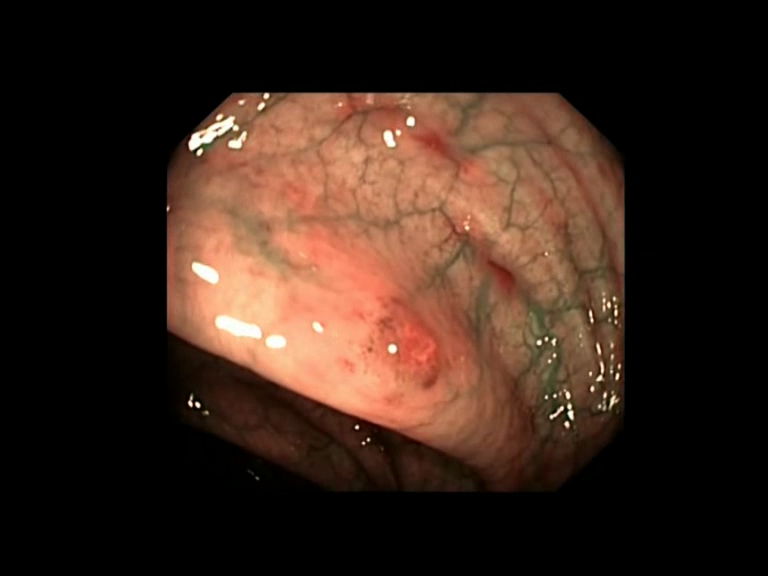

| Lesion | White Light Frame | NBI Frame | White Light Video | NBI Video | Camera Calibration |

| hyperplasic_01 |  |

|

WL.mp4 | NBI.mp4 | cam.xml |